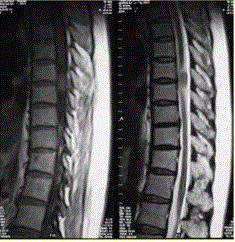

问题 患者女,52岁,颈部不适2年。MRI检查结果如下图。 观察所给出的MRI影像,对病变定位、定性诊断有意义的征象包括

选项 A.病变水平脊髓受压变细 B.病变与脊髓关系不清晰 C.病变上下方蛛网膜下腔增宽 D.矢状位示病变周围蛛网膜下腔无变化 E.脊髓向健侧移位 F.病变明显均匀强化 G.未见病变向椎间孔延伸

答案 ACEFG

解析 ACEFG